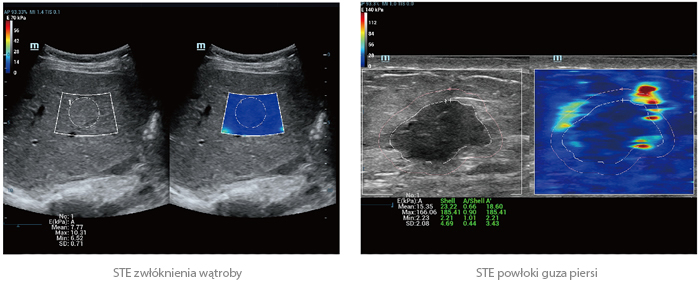

Elastografia Sound Touch (STE)

Zastosowana w aparacie Resona 7 technologia elastografii „Shear Wave” oparta jest na ekskluzywnym rozwiązaniu Firmy Mindray w postaci Ultra Wide Beam Tracking (Ultraszerokiej Wiązki), umożliwiając szybsze i bardziej precyzyjne obrazowanie. Zintegrowane narzędzia pomiarowe umożliwiają kompleksową, ilościową analizę cech elastyczności. Co więcej, funkcja STE nie wymaga Państwa udziału, gwarantując dobrą odtwarzalność badań USG i wysoką spójność wyników pomiarów ilościowych elastyczności.

20190703160142_4448